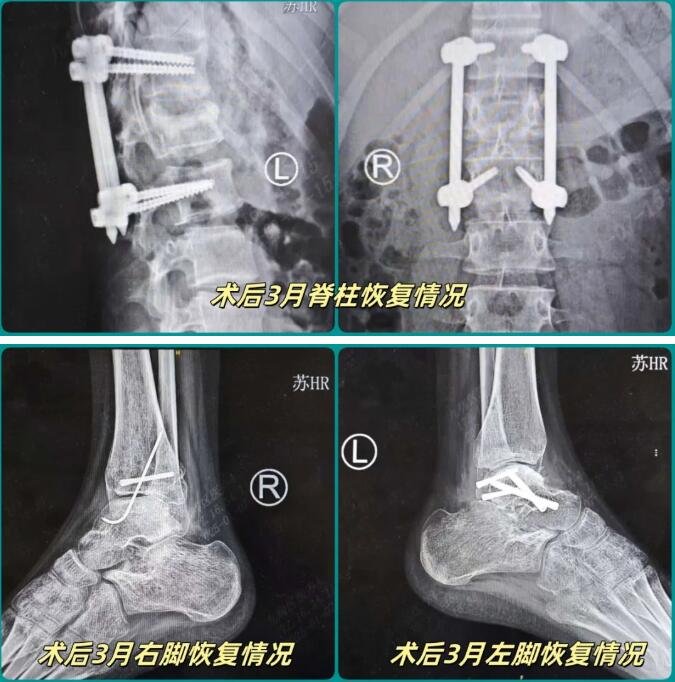

今年9月底的一天,14岁的小蕊不幸从三楼坠落到水泥地面上,造成腰椎前、中、后三柱骨折,双侧足踝粉碎性骨折,尤其是左踝距骨碎成了很多块。如此严重的伤情,很可能导致小蕊后半生在轮椅上度过。

然而,经过betway在线登陆多学科联合会诊治疗,仅仅一个多月后,她就能在家人的帮助下站立起来,经过近三个月的恢复,状态良好。为她复诊的石荣剑院长非常振奋:“看到孩子恢复得这么好,我们每一个参与过治疗的医生都为她由衷地高兴!”

当时,为了给小蕊制定最科学的治疗方案,betway在线登陆召集了足踝外科、脊柱外科、麻醉科等多个科室的专家共同讨论。考虑到小蕊两只脚踝均粉碎性骨折,脊柱上的伤情也非常严重,如果以传统的开放式手术治疗,一方面很难保证治疗效果,另一方面每个切口都可能达到十几厘米,以孩子的身体情况来说难以承受。经过周密计划,sararz医疗团队最终形成了“机器人+关节镜联合微创手术”的方案。经过十多个小时的持续手术,小蕊平安回到病房,并在一周后顺利出院(点击回顾详情)。

智慧 微创 快速康复

在复诊过程中,石荣剑一边为小蕊进行详细的检查,一边与家长沟通恢复情况。“不错!双脚和脊柱受伤的地方都愈合得不错。”石荣剑说,“通过机器人精准导航,结合微创的关节镜技术,当时孩子三处重伤,只打开了几个很小的‘针眼’,你看,现在这些‘针眼’都已经快看不见了。”更让石荣剑感到满意的是,在传统治疗的案例中,常常见到因肌腱受损、钢板阻碍而影响活动的情况,而通过智慧微创治疗,小蕊的脊柱、脚踝各部位活动能力恢复良好。